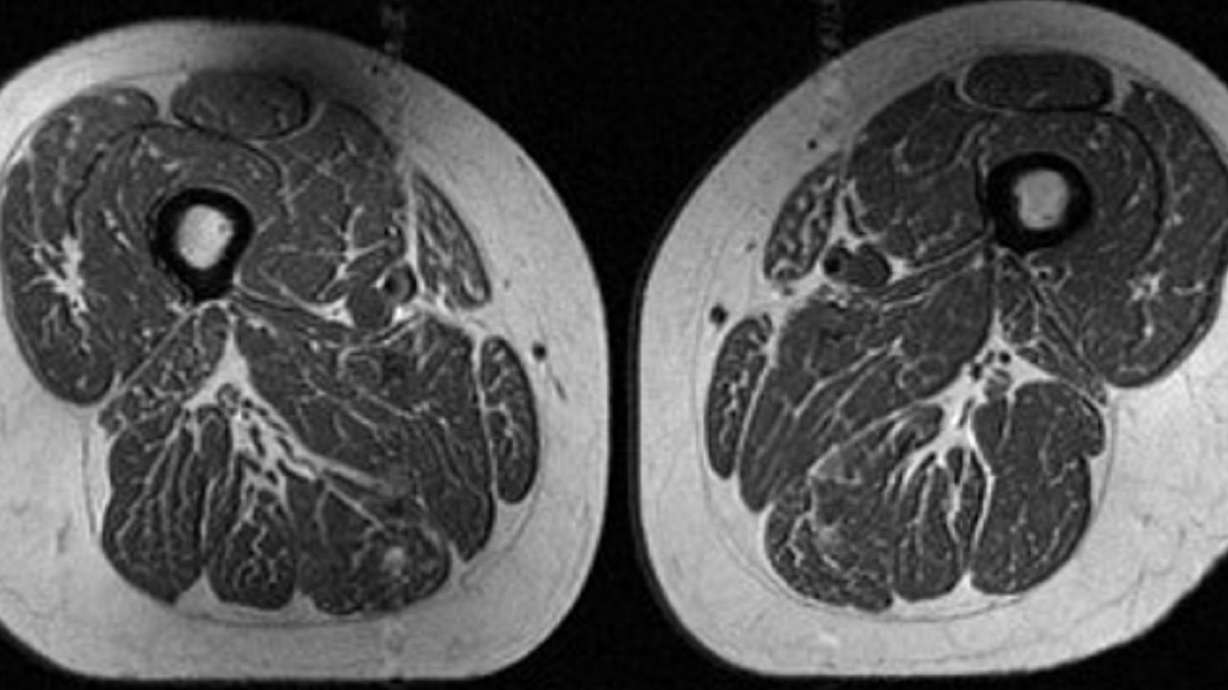

NEW YORK CITY — The image looks like a slice of highly marbled flesh, reminiscent of a high-end steak with abundant fine-grained streaks of fat. But that’s not dinner. It’s an MRI scan of the thigh of a 62-year-old woman who obtained 87% of her…